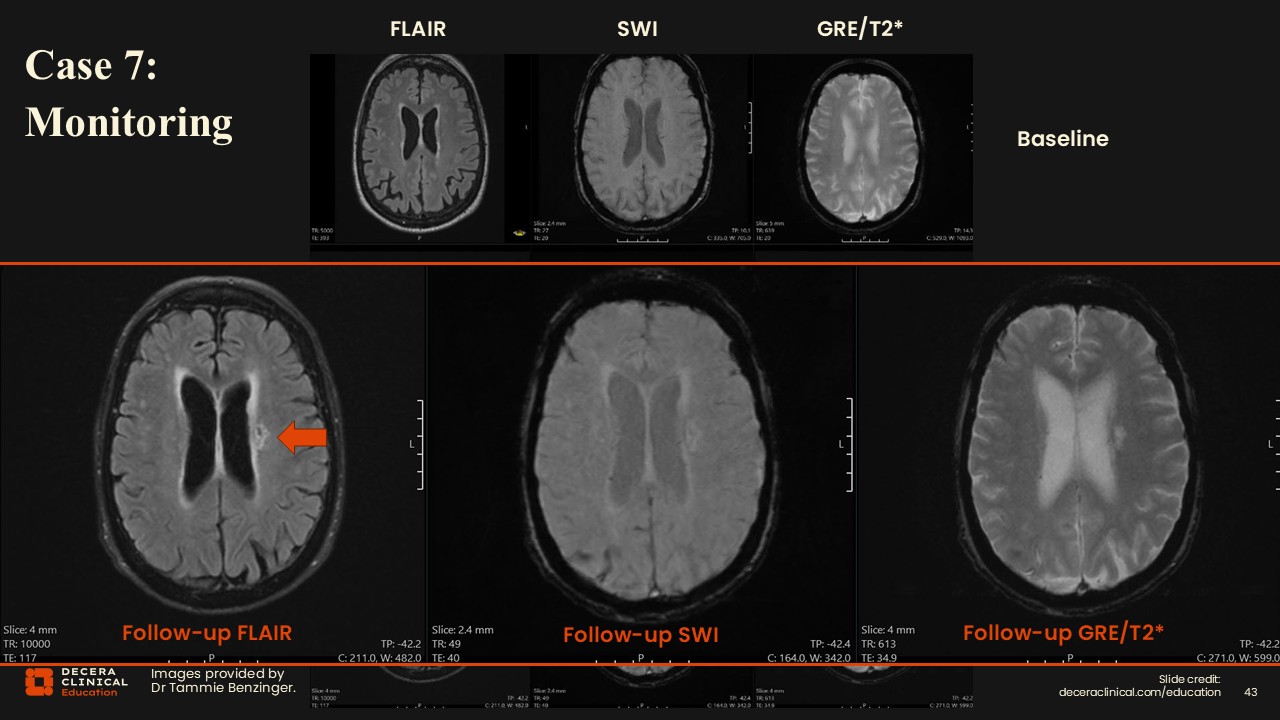

Case 7: Infarcts and Prior Siderosis

Dr Benzinger:

Another important feature to highlight showed up on another MRI in the left centrum semiovale. There is a lesion with FLAIR hyperintensity but suppresses centrally, which is not the location of his ARIA. And in fact, upon inspection of his other visits, what is seen is that when he developed that FLAIR hyperintensity, it had diffusion restriction. This is an important distinction.  ARIA and infarct have a lot of overlapping features on FLAIR. However, ARIA does not have diffusion restriction, and ARIA-related edema resolves over time. In this case, the patient had both processes occurring.

In the middle row, the right occipital FLAIR hyperintensity associated with the siderosis resolves on the follow-up visit. The finding in the left periventricular white matter corresponds to the infarct on a different visit. This highlights the need to watch for both of these things and distinguish ARIA from infarction; an infarct is not ARIA and requires standard stroke evaluation.

One additional finding in this case is on the very first baseline scan, there is 1 area of superficial siderosis, which is the same place where he develops ARIA later on. This reinforces the importance of carefully documenting superficial siderosis when reading that baseline MRI. In addition, when monitoring patients, areas of prior siderosis are important regions to scrutinize for subtle findings of new ARIA.

Case 7: Lessons Learned (Baseline Siderosis)

This case demonstrated siderosis at baseline and then the development of ARIA-E and ARIA-H all in the same region, once again illustrating that prior siderosis is predictive of future ARIA.

Case 7: Lessons Learned (ARIA Resolution and Vascular Comorbidities)

A second key lesson is that ARIA-E resolves on FLAIR, whereas an infarct does not. ARIA and ischemic infarcts can have overlapping features on FLAIR; DWI is essential to distinguish them.